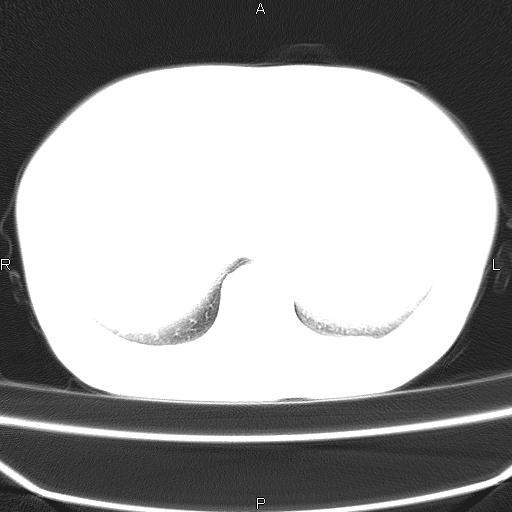

患者,女,66岁。健康体检胸部透视发现右上肺片状阴影。既往无不适,患者自诉三个月前曾有低热病史体温37.5左右一周。用药后缓解。至今无其它不适。请老师们指导指导。

考虑:右肺上叶周围型肺癌(分叶状肿块+砂粒状钙化+胸膜尾征)。

病灶见明显分叶、大小较大(大于3cm?),老年人,多考虑:肺癌,建议穿刺活检。

周围性肺癌,

周围性肺癌可能性大,建议增强

右肺上叶周围型肺癌可能性大。

考虑:右肺上叶周围型肺癌